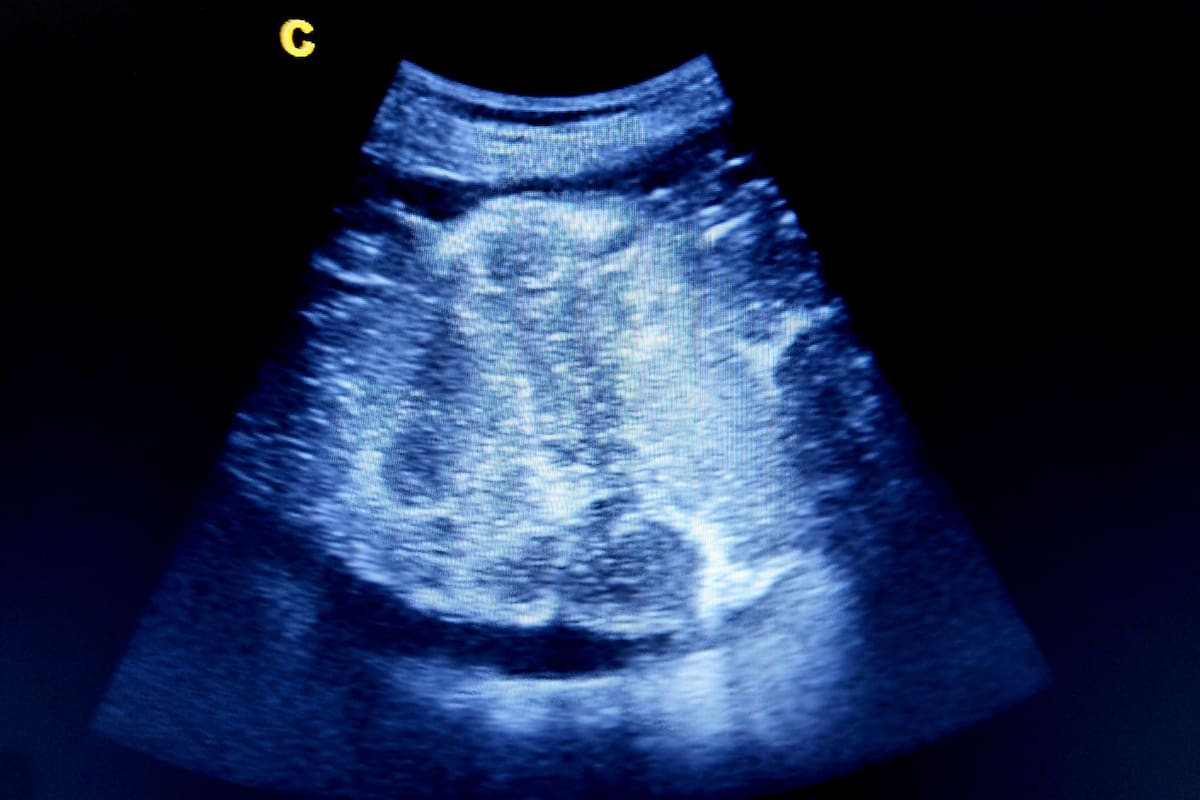

ESTADOS UNIDOS (AP).- Una nueva investigación indica que el coronavirus puede invadir y destruir la placenta, y provocar la muerte del feto en las mujeres infectadas. Es un resultado poco común en cualquier embarazo, pero las mujeres con Covid-19 tienen un mayor riesgo. Las autoridades creen que la vacunación puede ayudar a prevenir estos casos.

Él y sus colegas querían ver si ese era el caso de las muertes fetales en mujeres con Covid-19. Pero lo que encontraron fue casi lo contrario: era la placenta la que estaba infectada y se destruía en gran medida. “Muchos de estos casos tenían más del 90% de la placenta destruida, lo que resulta muy aterrador”, afirmó Schwartz.

El tejido normal de la placenta tiene un tono rojizo saludable y esponjoso. Los especímenes que estudiaron estaban rígidos, con decoloraciones oscuras de tejido muerto. Aunque otras infecciones pueden dañar la placenta en ocasiones, Schwartz dijo que nunca había visto que causaran una destrucción tan consistente y extensa.

La placenta es un órgano temporario que se forma y se adhiere al útero durante el embarazo. Se conecta con el cordón umbilical, proporcionando oxígeno y alimento del torrente sanguíneo de la madre.

Es probable que el virus llegara a la placenta a través del torrente sanguíneo, adhiriéndose a las células susceptibles y provocando depósitos de proteínas y una forma inusual de inflamación que bloqueó el flujo sanguíneo y el oxígeno. Esto, a su vez, provocó la muerte del tejido de la placenta y la asfixia, según los investigadores.